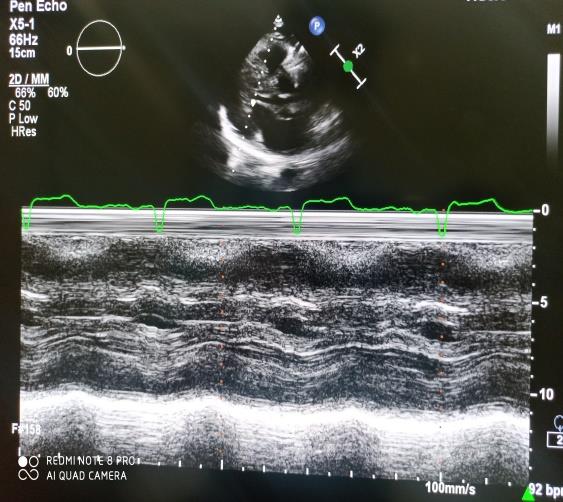

2D Echo imaging of similar patient when focused on looking for aortic valve it was showing gradient at LVOT. Being no Much hypertrophy of the Interventricular septum and posterior wall, the gradient was further evaluated. it was found that Papillary muscle was thickened to a greater extent, .which was creating a pressure gradient of 97 mm of hg, as shown in figure 1. Figure 2 also demonstrates the M mode showing compromised LV cavity at end Diastole. Similarly, in figure 1 we can see the calcified aortic Valve causing restriction of leaflet motion. patient was a known case of bicuspid aortic valve and i/v/o of severe nature (Peak/Mean Trans aortic gradient 89/45 mm of hg) of aortic stenosis. Gradients across mid cavity increased on doing Valsalva maneuver by the patient, which suggested a dynamic obstruction at mid cavity and the papillary muscle hypertrophy was the etiology for it. The thickness of the papillary muscle was 14 mm in our